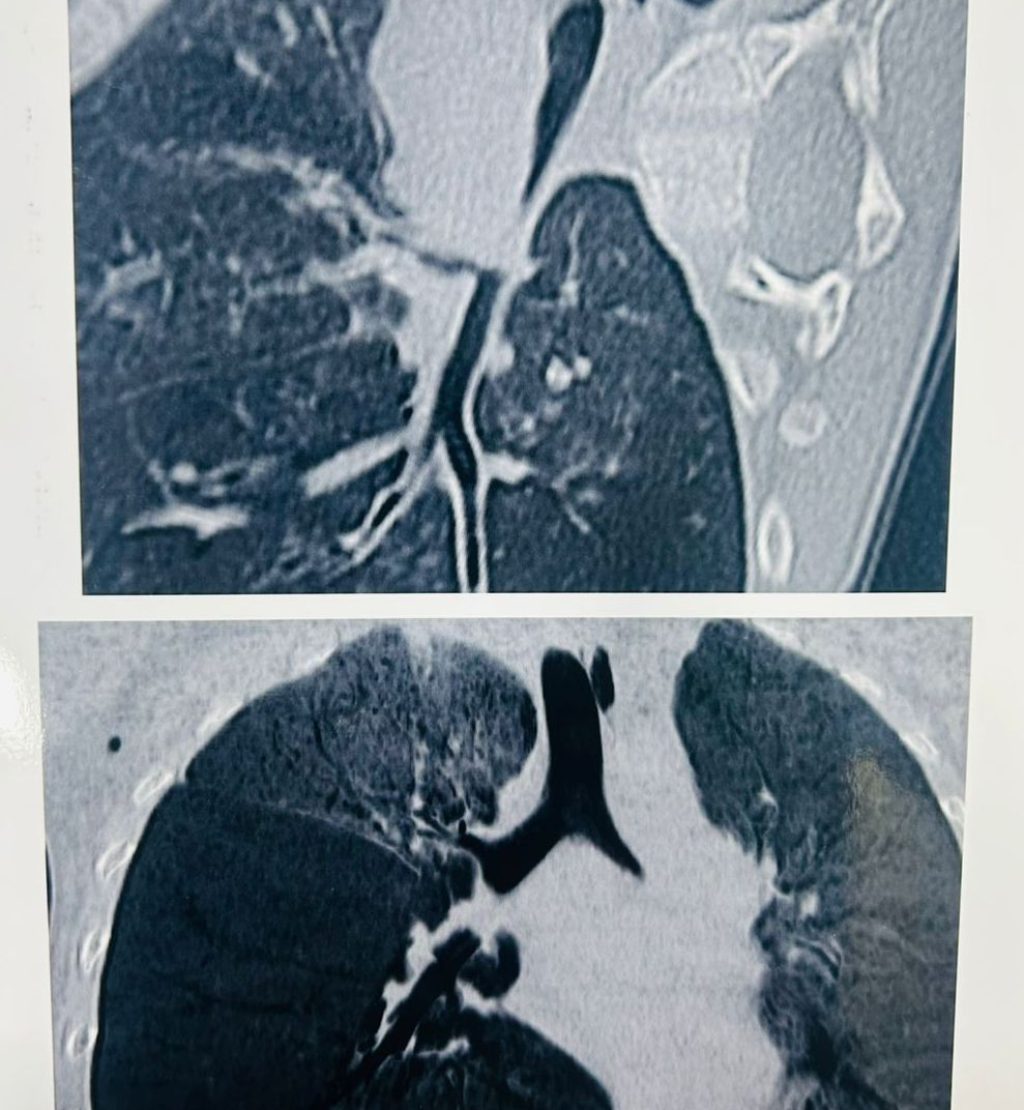

CT SCANNED SUGGESTIVE OF CLE, BRONCHOSCOPY FOUND FOREIGN BODY

(A 2-year-old boy, was admitted because of bad cough, cold ON AND OFF SINCE LAST 1 MONTH AND fever, and fast breathing OF RECENT ORIGIN . On checking, WE found that air was not going properly into his lungs, so he was given WAR oxygen, antibiotics, fluids, and nebulization. Blood tests showed infection. A chest X-ray showed lung infection and swelling of one lung. Since the problem started after eating groundnuts, doctors thought something might be stuck in his breathing pipe. A CT scan was done and showed narrowing of the airway AND  CHANGES OF CONGINITAL LOBAR EMPHYSEMA IN RIGHT SIDE WHICH NEED SURGICAL REMOVAL. So He was sent to a higher hospital FOR SAME, where SURGEON did a bronchoscopy FIRST and found a peanut stuck inside the airway. It was removed, and no surgery was needed. After removal, BABY improved quickly and recovered well.

Key lesson: (Always look at the child’s symptoms and condition, not only test reports.)